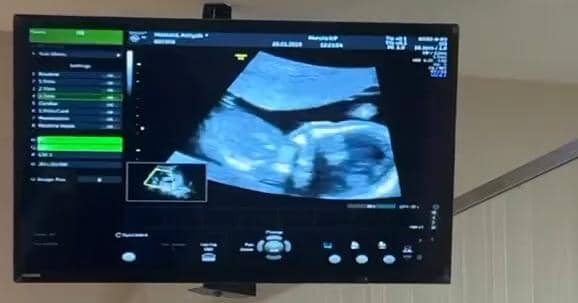

3. Momen saat Aaliyah melakukan USG

Kehamilan Aaliyah menjadi kejutan yang membahagiakan bagi Thariq, terlebih keduanya memang telah mendambakan anak. Aaliyah dan Thariq Halilintar sempat membagikan video saat melakukan USG di sebuah klinik kandungan.